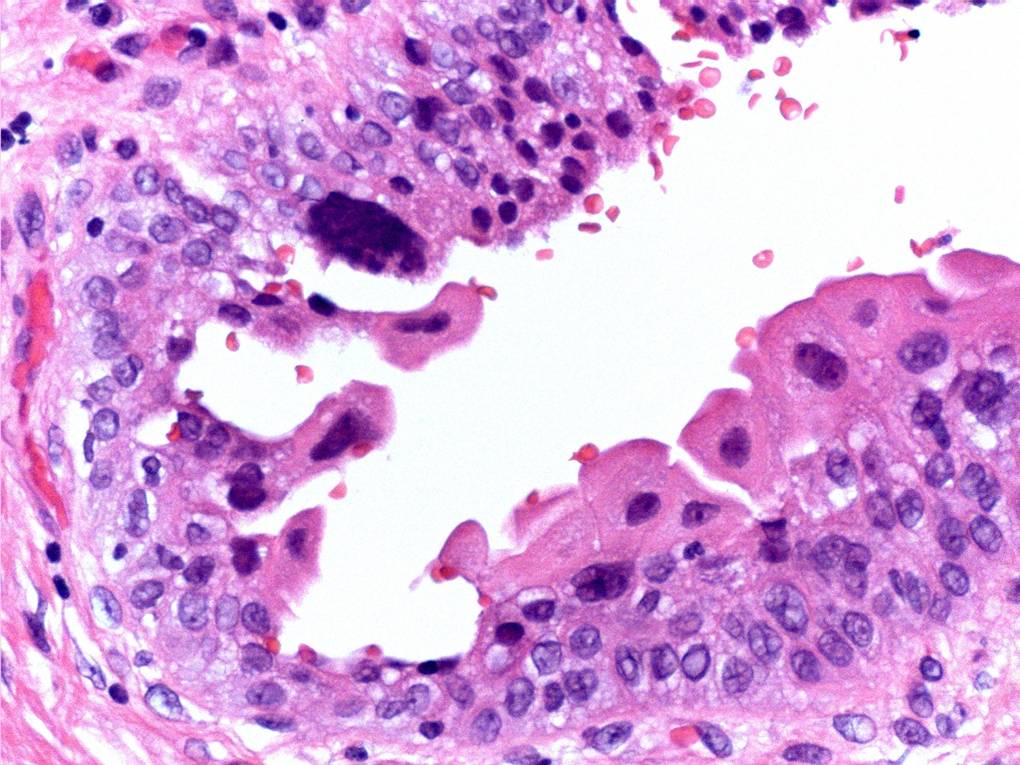

Consensus grade: Reactive atypia

Case description (by case creator):

The main change here is ‘degenerative’ nuclear atypia in a rather unusually prominent umbrella cell layer. The underlying urothelium shows mild reactive changes in places with some chronic inflammation in the lamina propria.